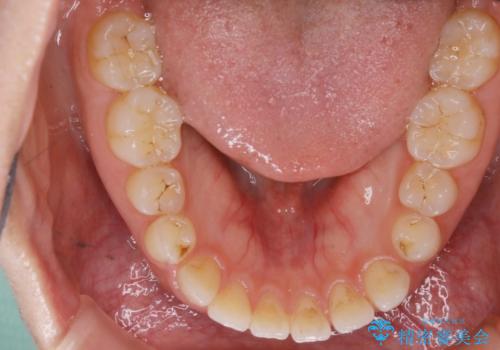

噛み合わせの治療

初診時の写真では一見噛み合わせには問題がないように見えても、実際に精密な検査を行うと改善すべき点が見つかる場合も多くあります。

当院では、矯正治療は見た目の改善が主目的ではなく機能面を改善し自然に長持ちする口腔内環境を整えることに重きを置く必要があると考えます。

しかしながら、こちらの理想だけを押し付けるだけが良い治療とは言えないので、患者様と治療のゴールの設定をよく話し合ったうえで方針を決定していくことが最も重要です。